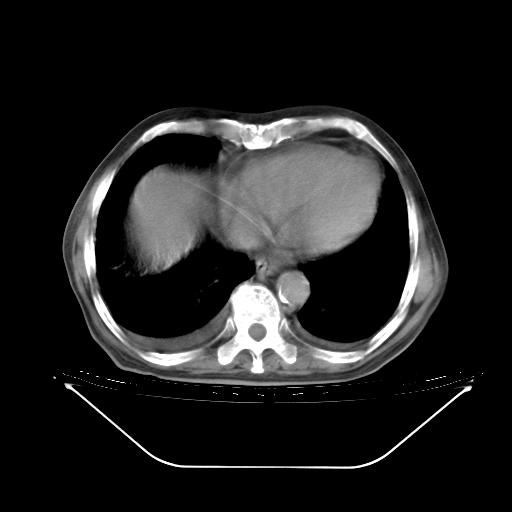

今天复查肺部CT,发现双肺广泛磨玻璃样改变。所以我把3月19日和5月9日相隔50天的肺部CT上传。请大家会诊。

5月9日肺部CT(在4月27日齐鲁医院肺部CT描述部分肺组织磨玻璃样改变,12天后肺组织广泛磨玻璃样改变)

2009年5月9日肺部CT